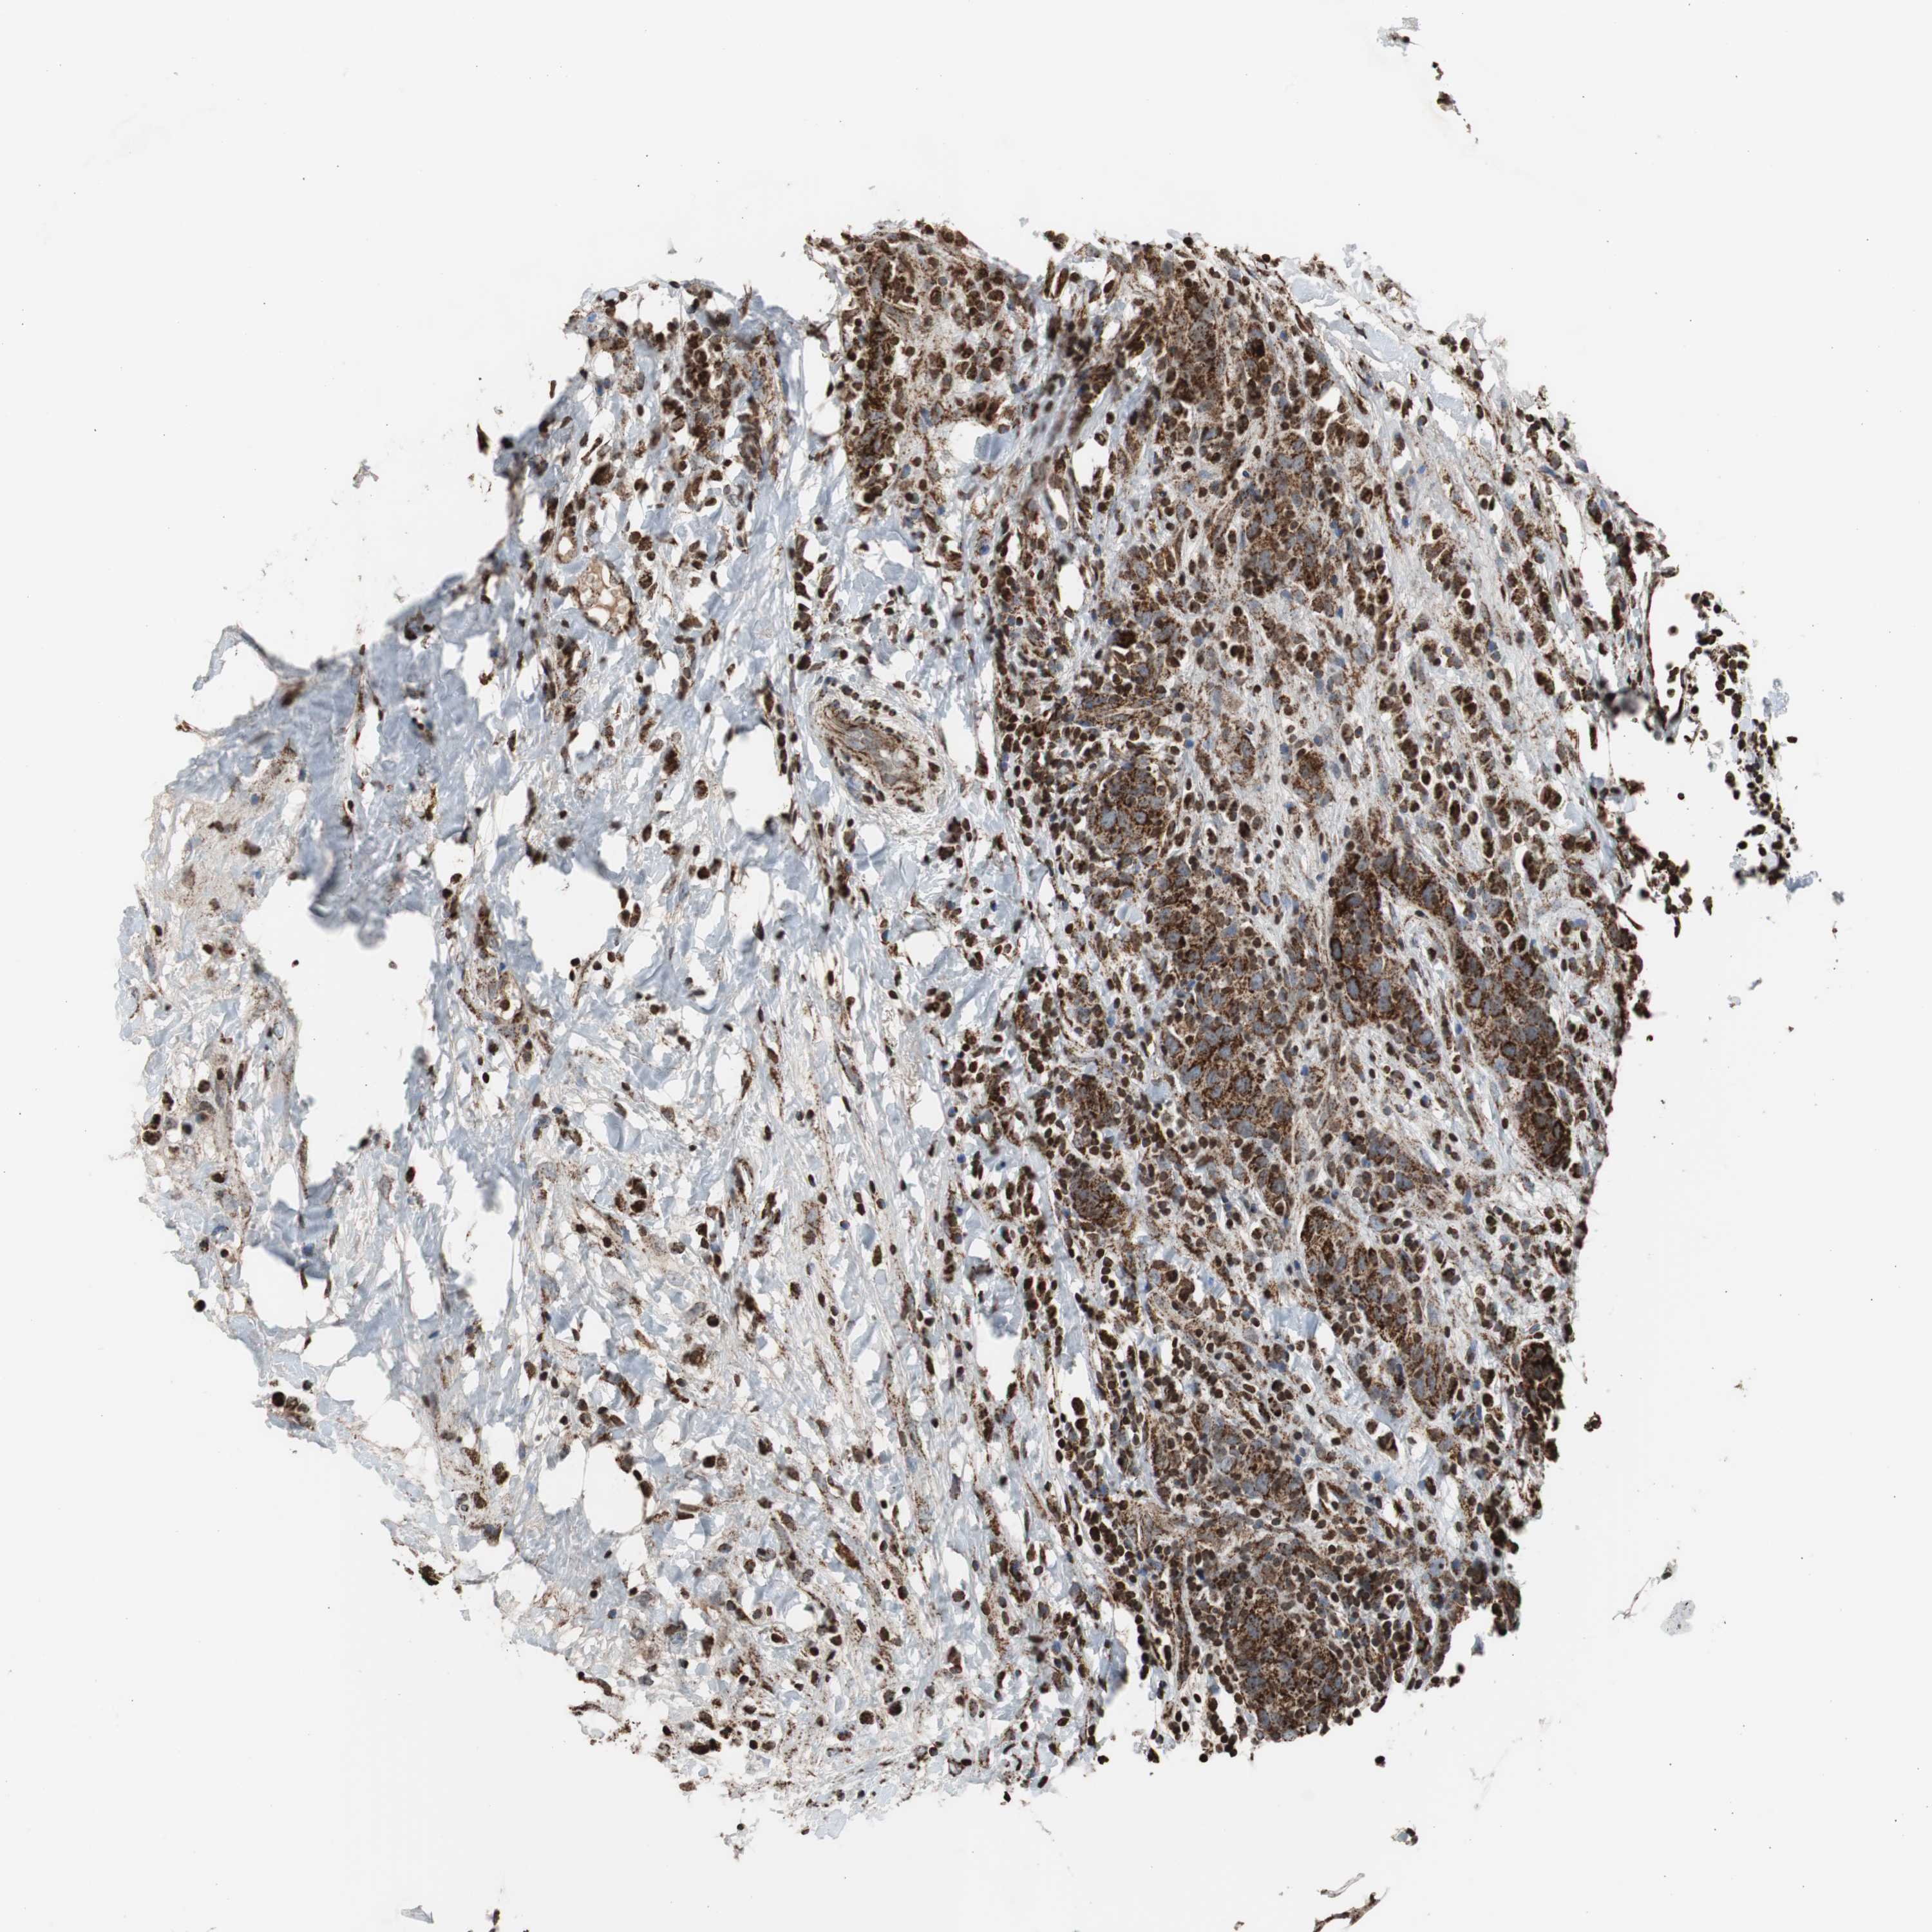

CANCER BREAST CANCER Show tissue menu

BRCA TCGA BRCA VALIDATION PROTEIN EXPRESSION